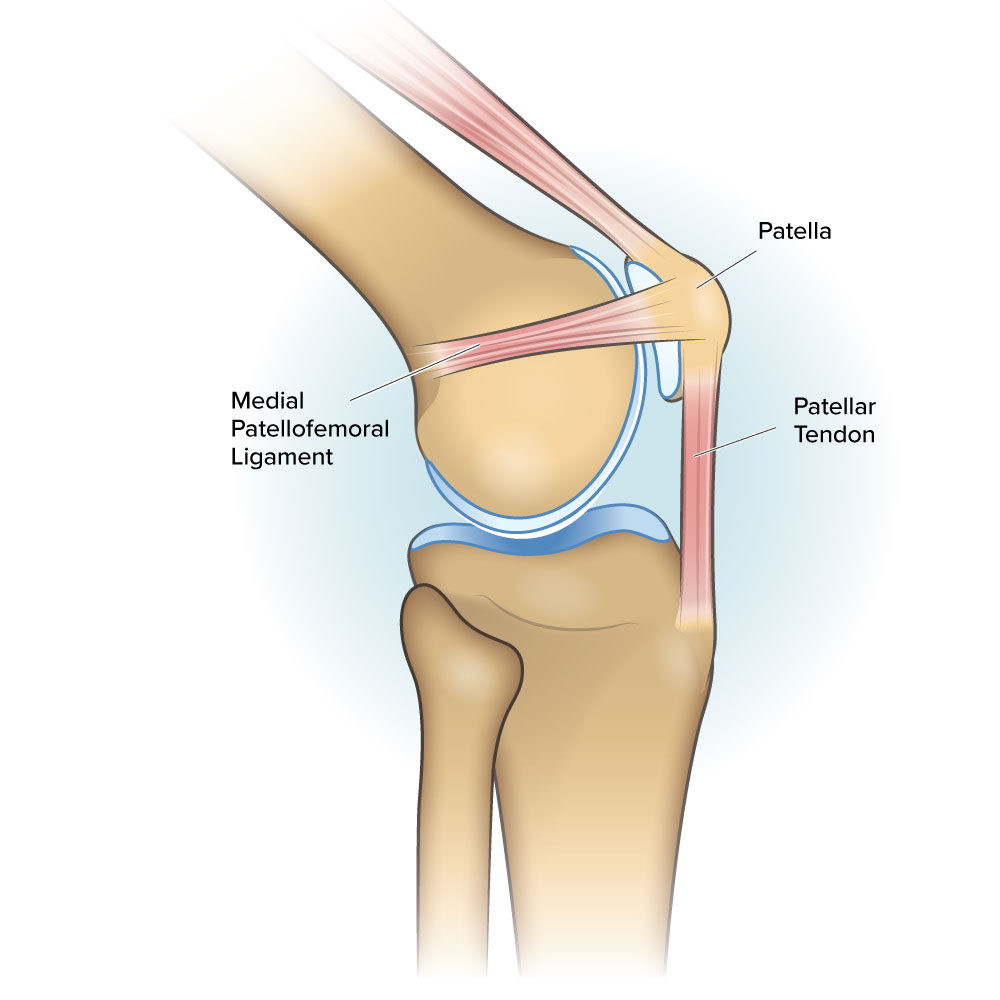

MPFL The Little Ligament That Could ProActive Physical Therapy online, Medial Patello Femoral Ligament MPFL Reconstruction online, Patellofemoral Ligament Reconstruction Knee Surgeon South online, Arthroscopic reconstruction of the medial patellofemoral ligament online, Medial Patellofemoral Ligament Tears Minneapolis MN Sports online, Medial Patellofemoral Ligament Reconstruction Techniques online, Patellofemoral Instability in the Skeletally Immature Patient A online, Medial Patellofemoral Ligament Surgery In Tamilnadu online, Physical Therapy for Medial Patellofemoral Ligament Injury online, PDF Management of medial patellofemoral ligament injury A case online, Medial Patellofemoral Ligament Injury MPFL Specialist Sugar online, Arthroscopy Journal on X online, The Medial Patellofemoral Ligament of the Knee by Nabil Ebraheim online, Figure 4 from The medial patellofemoral ligament Review of the online, Medial patellofemoral ligament reconstruction technique online, Graphic illustration of double bundle medial patellofemoral online, MPFL reconstruction animation online, What is the difference between MCL and MPFL ligaments and does online, Dynamic Anatomical Reconstruction of Medial Patellofemoral online, MPFL Injury Medial Patellofemoral Ligament MPFL Tear online, Your Patellofemoral Ligaments and Cartilage Spring Loaded Technology online, MPFL Reconstruction Hertfordshire Patellar Instability online, Medial Patellofemoral Ligament Reconstruction Complete Orthopedics online, Medium to long term outcomes of medial patellofemoral ligament online, Figure Diagram of the patellofemoral ligaments. Contributed by online, Medial Patellofemoral Ligament Tear Moreno Valley CA MPFL online, Medial Patellofemoral Ligament Of The Knee Anatomy Everything You Need To Know Dr. Nabil Ebraheim online, The Medial Patellofemoral Ligament MPFL The Basics BSM Foundation online, Medial Patellofemoral Ligament MPFL Reconstruction Knee online, Medial Patellofemoral Ligament MPFL Gorav Datta online, Medial Patellofemoral Ligament Reconstruction Sydney Knee online, Medial Patellofemoral Ligament Injury Recovery Capital Area PT online, Medial Patellofemoral Ligament MPFL Reconstruction HSS online, Medial Patellofemoral Ligament Injury MPFL Tear MPFL online, Medial Patellofemoral Ligament MPFL Physiopedia online, Product Info: Medial patellofemoral ligament online.